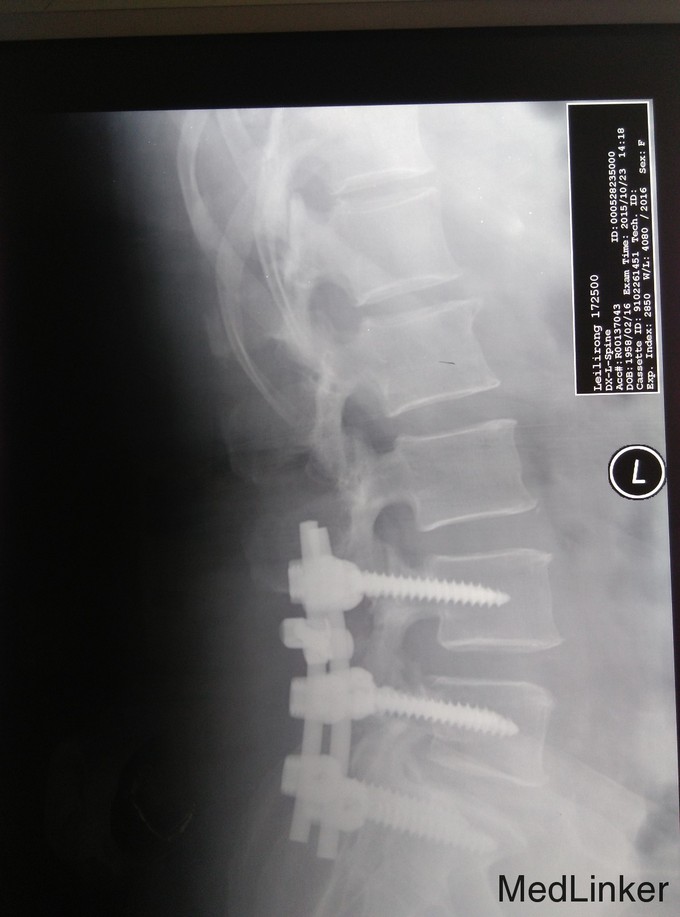

诊断:腰椎管狭窄症、腰椎间盘突出、腰椎骨关节病 治疗:入院后完善相关检查,无明显手术禁忌症,于手术室全麻下行腰4-5、腰5-骶1椎板切除、椎管减压、椎弓根内固定术,

术后给予抗炎、抗感染,消肿、止痛对症治疗,术后第1天拔出引流管,嘱患者腰围保护下地,适度功能锻炼,术后两周拆线,出院,术后患者自诉双下肢麻木大部分缓解,效果良好。